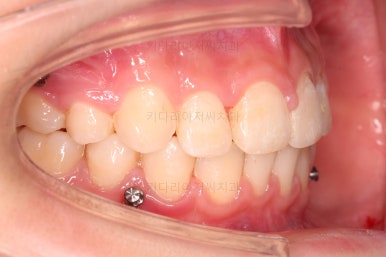

연산동치아교정 선택한 장치는 엠파워 클리어라고 하는 자가결찰 세라믹 장치입니다.

치아 갯수를 맞추고 튀어나온 앞니를 넣기 위해서 윗니 중간의 작은 어금니를 발치를 했고요.

윗니는 틈을 점점 줄여가고요.

아랫니는 중간에 오히려 틈이 생기고 있죠?

이런 효과로 위아래 앞니는 급속도로 가까워지게 됩니다.

아랫니는 이후에 어금니를 앞으로 당겨오면서 빈공간을 줄여 나갑니다.

교합이 점점 맞아가네요.

윗니 뽑은 자리도 거의 다 줄었습니다.